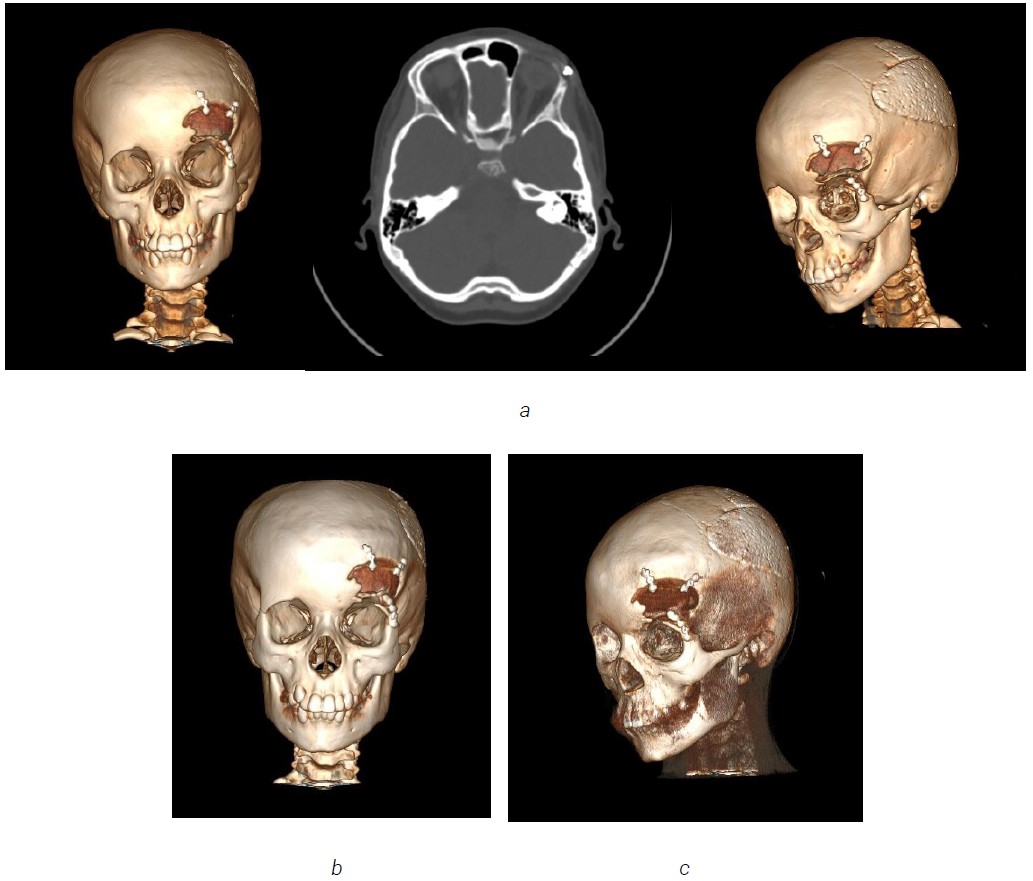

In the postoperative period, the patient received antibacterial, infusion and symptomatic therapy. Healing by primary intention with the bone configuration looking normal. The patient was discharge home after 2 weeks from the operation day. He was monitored each year in RCCH by a follow up MSCT of skull. Recurrent episodes of this condition was revealed in 2022. MSCT showed evidence of bone regeneration and recurrence, with “hazy ground glass” appearance again in the same treated area in the left frontal bone region. (Figure 11). In 2025, a MSCT has been done again, and we noticed fast progression of FD in the same affected area (Figures 12, 13).

Fig. 11. MSCT scan showing recurrence of FD on the left frontal bone in 2022

Fig. 12. MSCT revealed of fibrous dysplasia on the left frontal bone in 2025

Fig. 13. Axial and sagittal computed tomographic image exhibiting characteristic ground-glass opacification of fibrous dysplasia involving the left frontal bones in 2025

A 9 year old girl presented volume formation and growth in the right frontal bone in the winter of 2021. Due to no complain by this formation, the patient did not received any treatment back then. The patient was admitted to the RCCH for the first time for examination and treatment 2022, where a MSCT was done, due to notable facial asymmetry.

MSCT of the skull shows monostatic fibrous dysplasia in the right frontal bone (5x5 cm). A focus of fibrous dysplasia with damage to the frontal bone and orbital roof was revealed. Additionally, edema and deformity in the right frontal bone was observed (Figure 14).

Fig. 14. The edema and deformity in the right frontal bone. a — 3D computed tomography image shows increased dimensions of the right frontal bone; b — axial computed tomography image with expansion of right frontal bone

Fig. 15. Post-operation MSCT with three-dimensional reconstruction check-up

A split graft from the cranial vault was planned. A 5×5 cm fragment was taken from the adjacent area of the unchanged frontal bone, which was subsequently split into 2 fragments with the return of the inner cortical plate to the donor area, and the outer cortical layer was cut into 3 fragments and re-modeled. The graft fragments were fixed to each other and to the skull bones (Figure 15).